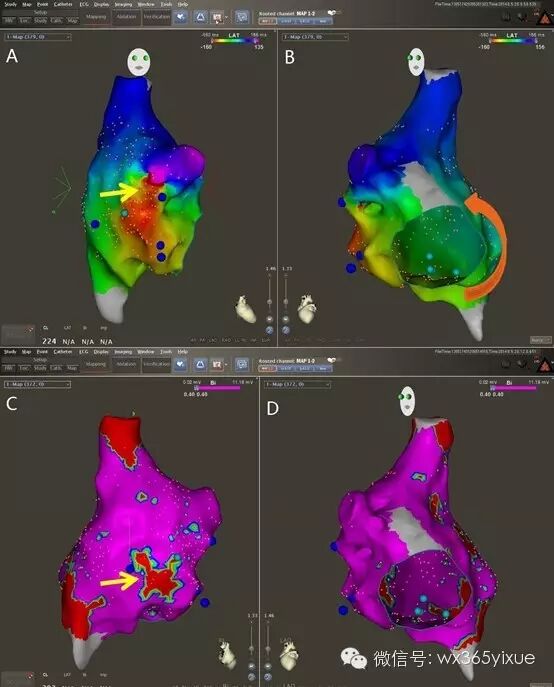

1.高密度标测明确心动过速机制:不论是对于局灶或是大折返房性心动过速,减少射线及手术时间的关键在于尽快明确心动过速机制,相对其他心律失常,更需要最大限度地利用好三维系统的电解剖标测功能20。由于房速的激动起源及传导模式变化多端,电生理检查首先需要鉴别心动过速是起源于左房还是右房,即使冠状窦电图等明确提示左房起源可能性大,也建议常规先标测右房,标测右房的方法可参考前文。排除右房起源或参与心动过速后,方穿间隔进入左房。由于左房内结构相对复杂,电激动的传导模式也更为多样,过于粗略的标测方式容易遗漏重要位点的信息,给术者的判断带来困难甚至误导诊断,因此在左房进行激动标测时需要强调高密度标测,即在心腔内至少需要采集300个激动点,在重点部位如房间隔、顶部、二尖瓣环等部位常常需要导管重复停留及采点21,22(图5-1)。高密度标测的达成,除了术者快速、准确移动导管外,具有多个标测电极的导管成为必要工具,最常用的为用于房颤消融的LASSO环状标测电极。为了尽量避免错误的激动顺序点,建模及标测时对导管在心房壁各处的贴靠也提出更高的要求,同时要求配合操作的人员能够快速过滤无效或者无用的信号点。同前文所述右房房扑的建模和标测相同,仅在需要确认导管位置等必要情况下方才使用X线透视。

图5-1 左心房高密度标测 上半图为左心房电压标测图、高密度标测下发现左房后壁存在小片异常电压区域,下半图为心动过速下左心房激动顺序图,提示围绕二尖瓣环折返的房性心动过速。

3.准确判断消融位点及消融:明确心动过速的起源和关键部位后,同样需要在三维模型中规划消融方式,X线透视可作为辅助。对于局灶的房速,在关键点消融往往能迅速终止心动过速,但异位兴奋点往往并非真的只有一个“点”,需要将射频能量覆盖周围的小片区域以避免复发(图5-2)。对于肺静脉内起源的房性心动过速,可靠地消融方式是行该侧的环肺静脉电隔离。对于大折返房速,必须在折返峡部做可靠地线性隔离,根据不同部位和方式的折返,顶部线、二尖瓣峡部线、前壁线是常用的线性消融方式(图5-3)。需要重视的是消融终点必须是消融线两侧的双向阻滞而不仅仅是消融终止及不再被诱发。除非心室率过快导致患者无法耐受,应选择在心动过速发作状态下进行消融。

图5-2 起源自左房前壁的房性心动过速 上半图为高密度激动顺序图,明确为起源自左房前壁靠近心耳根部的局灶房性心动过速;下半图示消融靶点,在激动最早部位放电消融即刻终止心动过速,最终以片状消融覆盖了最早激动区域

图5-3 运用激动顺序及基质标测指导消融左房房性心动过速 图A为左房激动顺序图,提示激动环绕左房前后折返;图B为电压标测图,发现顶部有一异常电压区域;图C为消融靶点图,在顶部异常电压区域消融即终止心动过速,最终行顶部线的消融并验证双向阻滞。